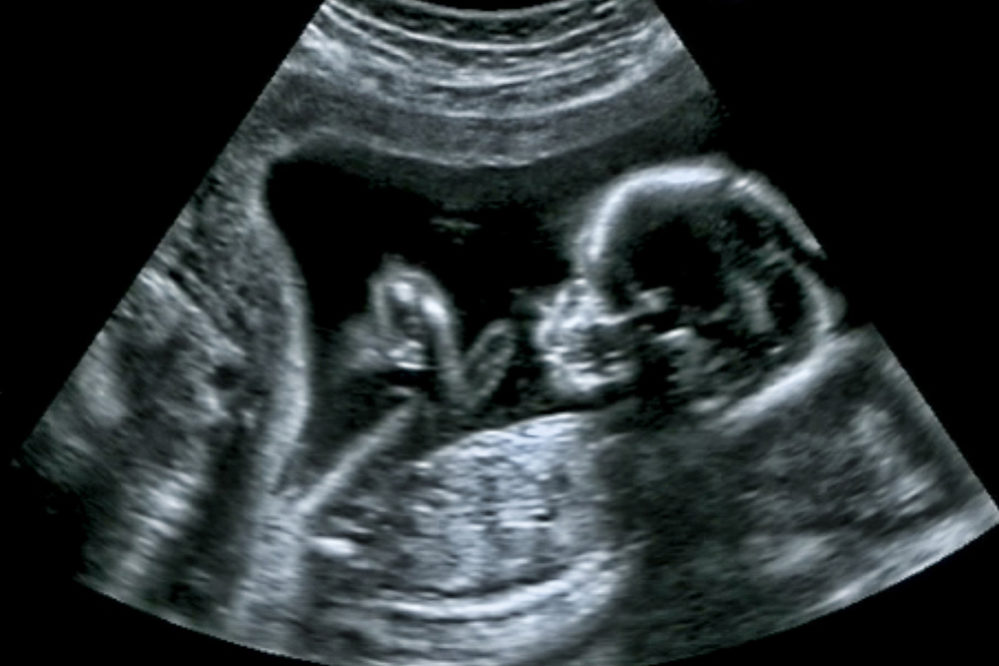

Dois dias depois fizemos o primeiro ultrassom e a felicidade só aumentou ao ouvir seu coração pela primeira vez. Estava de 7 semanas e me perguntei como demorei tanto pra descobrir. Nos dias seguintes contamos aos mais próximos, meu Deus, quanta felicidade, quanto amor… Eu nem sabia que éramos tão amados por tanta gente!

Primeiro morfológico foi perfeito, meu bebê estava saudável e tivemos a previsão de ser um menino. Eu só sabia agradecer a Deus!

Terceiro ultrassom, confirmado! Nosso Rafa estava a caminho com muita saúde! Eu só podia agradecer a Deus! Tudo ia bem e estava orgulhosa das mudanças no meu corpo, minha barriga demorou a aparecer, mas o que me importava era que o Rafa estava muito bem, com líquido amniótico em quantidade normal.

22/08 – Chegou o dia do morfológico de segundo trimestre, o resultado mostrou que eu estava com arritmia cardíaca e que o Rafa tinha um pequeno problema no rim. Me preocupei, mas eu sabia que acima de qualquer coisa existe um Deus maravilhoso que nos guia, minha oração mudou um pouco, mas agradeci a Deus, pedi misericórdia e me lembro de ter dito: mas que prevaleça a Sua vontade na minha vida. E prevaleceu.

Em mais ou menos 1 hora fui para o ultrassom, ouvi o coração do Rafa pela última vez e ainda consegui vê-lo

naquela tela escura. Pedi forças pra Deus! As dores eram insuportáveis e a cada movimento que eu fazia, conseguia sentir uma grande quantidade de sangue saindo de mim.